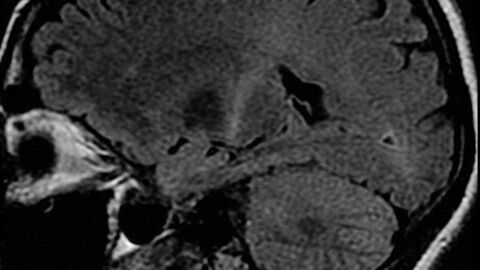

Parkinson's disease is a degenerative disease characterized by the progressive loss of neurons, resulting in multiple motor disorders. It affects an area of the brain responsible for making and releasing a neurotransmitter called dopamine, which plays a vital role in controlling body movement. The disease occurs most often in people over the age of sixty. It is the second most common neurodegenerative disease just after Alzheimer's disease.